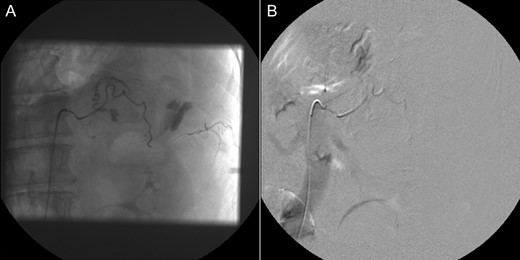

A 60-year-old male presented with pain at the left upper quadrant and left flank, radiating to the back. The patient had known hypertension and had suffered a myocardial infarction a year ago with stent insertion, now being on aspirin and clopidogrel. Upon admission all observations were normal. On examination, tenderness with guarding were noted at the left upper quadrant. Giordano sign was strongly elicited. Laboratory investigations were normal other than leukocytosis (WBC: 15.300, 89% neutrophils). US was unremarkable and CT scan revealed a retroperitoneal hematoma, at the site of the left adrenal gland, associated with extravasation of contrast (Fig. 3). The patient underwent angiography and active bleeding was confirmed from the middle adrenal artery which was successfully embolized microspheres (Fig. 4). The patient was transferred to ICU. He remained hemodynamically stable, without requiring blood transfusion. Four days later he was transferred to the ward. Pheochromocytoma was excluded with VMA, while ACTH and cortisol measurements ruled out adrenal insufficiency. Clopidogrel was permanently discontinued. The patient was discharged after 14 days and follow-up MRI confirmed hematoma resolution excluding an underlying mass.

Selective adrenal artery angiography showing active extravasation from the middle adrenal artery (A) and subsequent successful embolization (B).